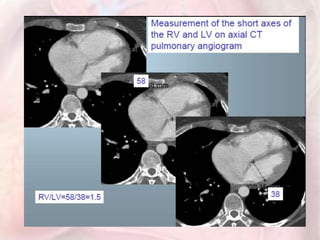

CT evidence of RV dysfunction

•RV dilation

•RV/LV short axis >1= pulmonary

hypertension

•RV/LV short axis >1.5= severe PE

•Leftward septal bowing